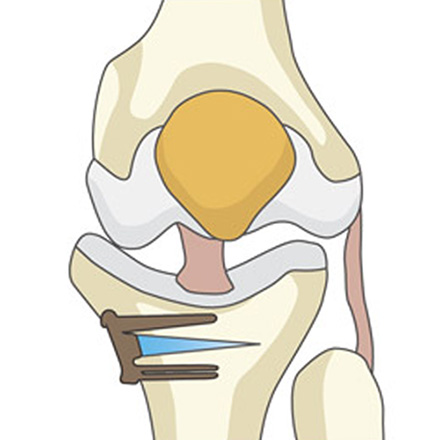

04

바로잡은 각도가 잘 유지되도록 금속 플레이트와 나사로 단단히 고정합니다.